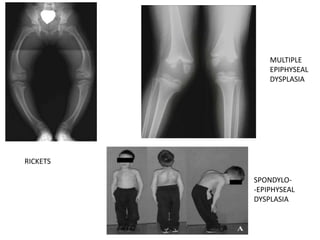

DIFFERENTIAL DIAGNOSIS

• Persistent physiological varus

• Rickets

• osteogenesis imperfecta

• Multiple Episphyseal Dysplasia(fairbanks d/s)

• Spondyloepiphyseal dysplasia

• metaphyseal dysostosis (Schmidt, Jansen)

• focal fibrocartilaginous defect

• thrombocytopenia absent radius

• proximal tibia physeal injury (radiation, infection,

trauma)

RICKETS

MULTIPLE

EPIPHYSEAL

DYSPLASIA

SPONDYLO-

-EPIPHYSEAL